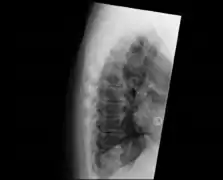

Confluent ossification of multiple contiguous vertebral bodies in diffuse idiopathic skeletal hyperostosis (DISH)

"Melted candle wax" appearance of calcification and ossification in diffuse idiopathic skeletal hyperostosis (DISH). Note the preponderance on the patient's left side (right side of image).